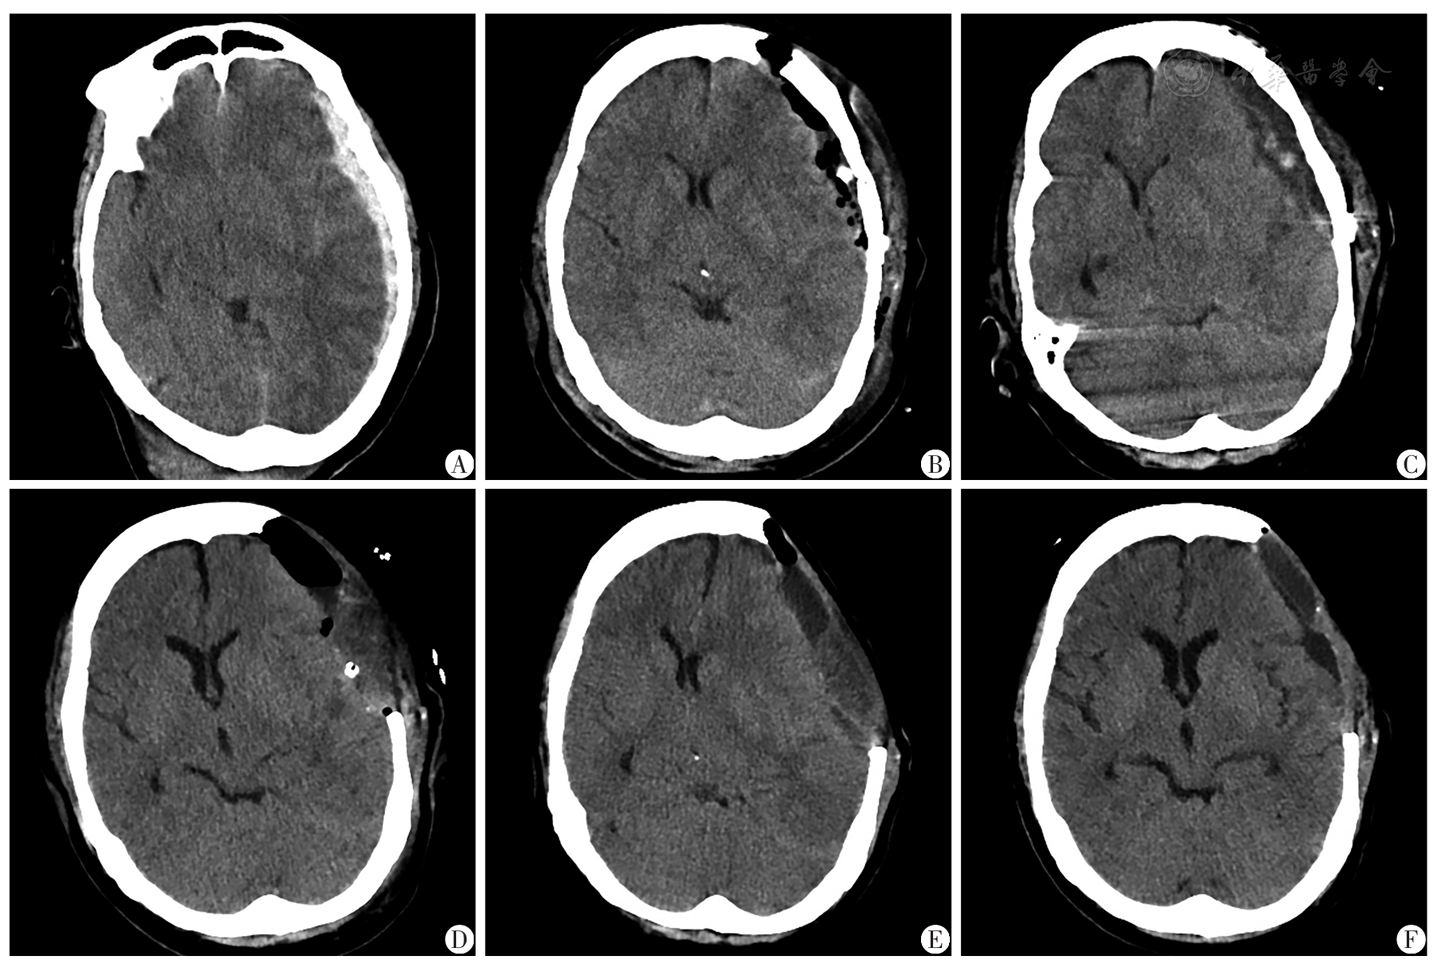

图2 创伤性硬膜下血肿后CCSFH致脑疝患者(病例2)手术前后的影像学资料A:首次手术前CT示左侧额颞顶部硬膜下血肿;B:首次手术后CT示硬膜下血肿清除彻底,骨瓣下积气,中线移位改善;C:2次手术前CT示脑膨起不良,皮层脑沟消失,骨瓣下积液,中线移位16.00 mm,基底池消失;D:二次手术后CT示脑膨起仍欠佳,中线移位明显改善;E:经术腔引流、甘露醇降颅压后,复查CT示反常性脑疝;F:患者取平卧位后3 d,CT示中线基本居中,皮层脑沟清晰;CCSFH:严重脑脊液低容量

Fig.2 Pre- and post-surgical imaging data in the patient with cerebral herniation caused by CCSFH after traumatic subdural hematoma (case 2)